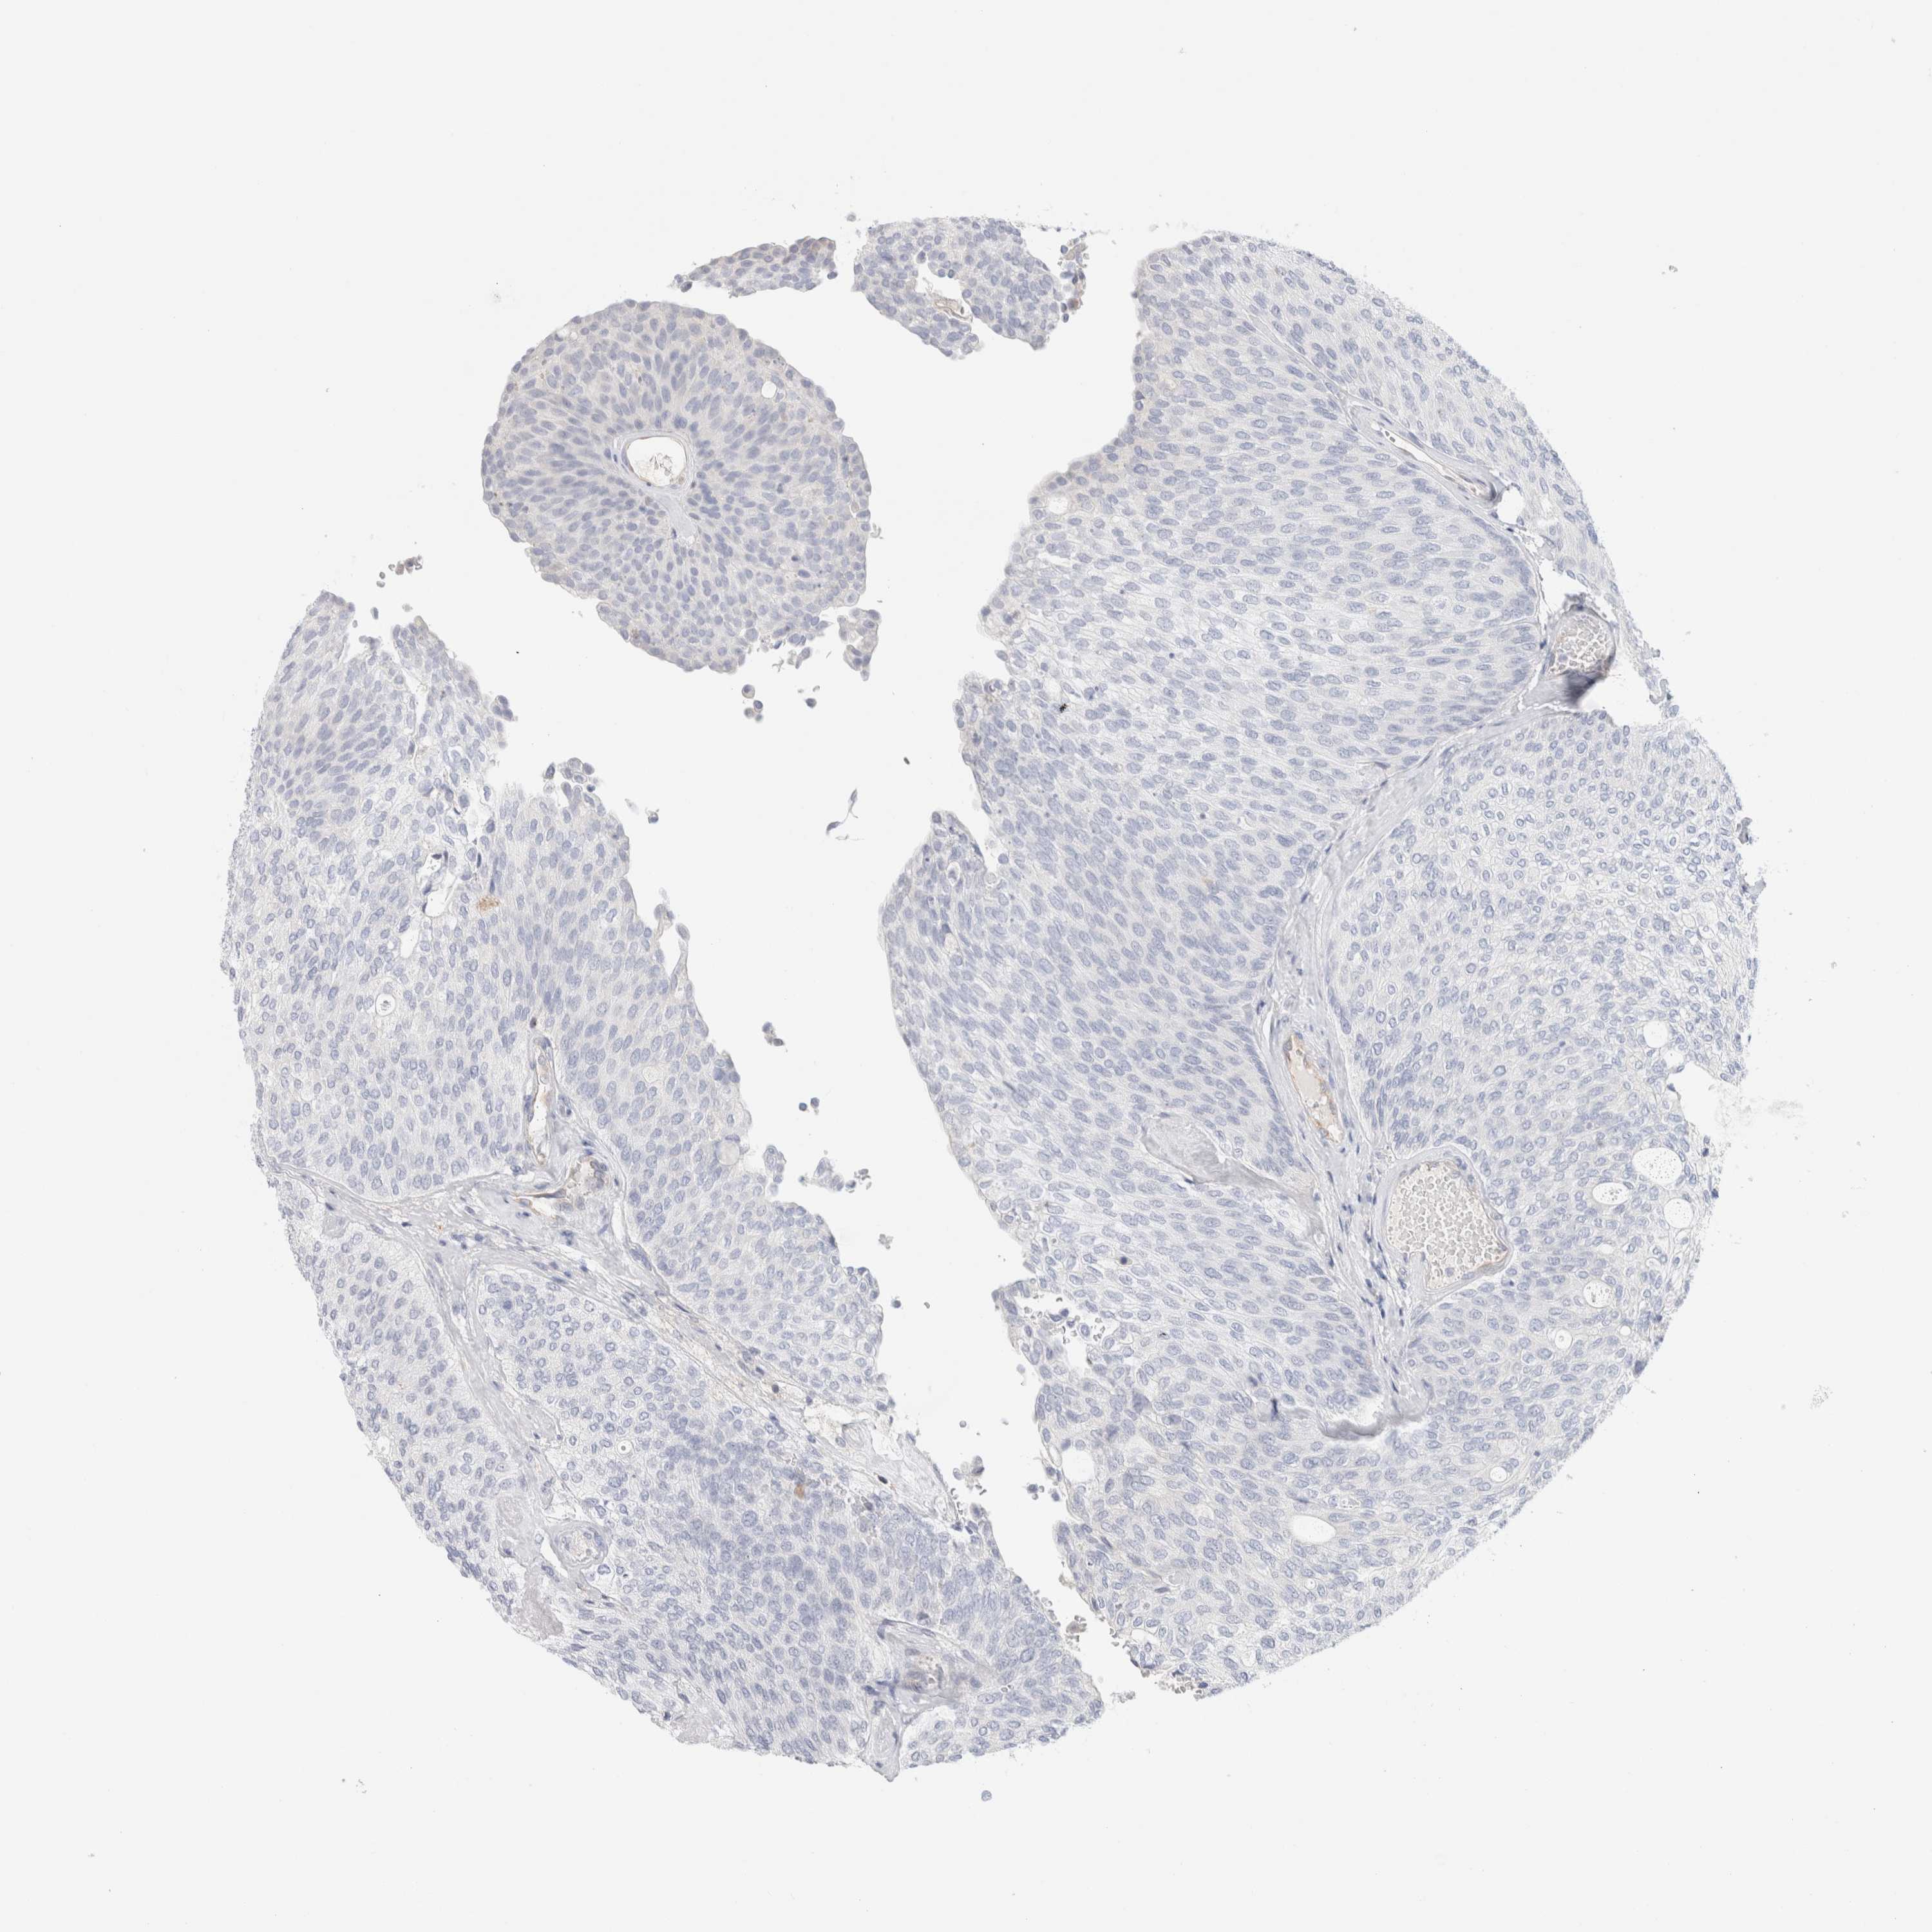

UROTHELIAL CANCER - Protein expressioni

A mouse-over function shows sample information and annotation data. Click on an image to view it in a full screen mode. Samples can be filtered based on level of antibody staining by selecting one or several of the following categories: high, medium, low and not detected. The assay and annotation is described here.

Note that samples used for immunohistochemistry by the Human Protein Atlas do not correspond to samples in the TCGA dataset.

Antibody stainingi

Antibody staining in the annotated cell types in the current human tissue is reported as not detected, low, medium, or high, based on conventional immunohistochemistry profiling in selected tissues. This score is based on the combination of the staining intensity and fraction of stained cells.

Each image is clickable and will lead to virtual microscopy that enables deeper exploration of all samples and also displays staining intensity scores, fraction scores and subcellular localization as well as patient and tissue information for each sample.

Antibody HPA026488

Antibody HPA028425

Antibody CAB011203

Urothelial carcinoma, Low grade

Urothelial carcinoma, High grade